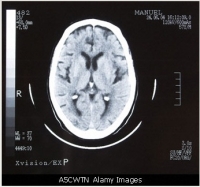

A tomografia computadorizada é mais popular nos Estados Unidos do que na Europa e é indicada em casos nos quais os médicos necessitam da tecnologia para "reconstruir" tridimensionalmente órgãos internos, vasos, ossos e tumores.